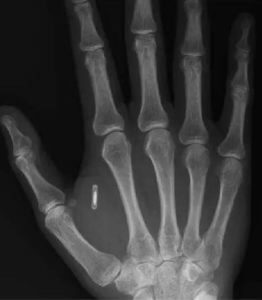

Particolarmente diffusa nella “comunità dei biohacker”, poi, è la pratica dell’implanting, ovvero dell’impianto di dispostivi nel corpo umano, aspetto, questo, che ci riporta nuovamente al concetto di cyborg. Tipico è il caso dell’innesto sottopelle di chip RFID, che consentono di aprire porte, pagare merci e memorizzare informazioni di contatto o dell’impianto di piccoli magneti sottocutanei che permettono all’essere umano di sollevare oggetti metallici e addirittura di percepire i campi magnetici.

La radiografia di una mano in cui è stato impiantato un chip RFID